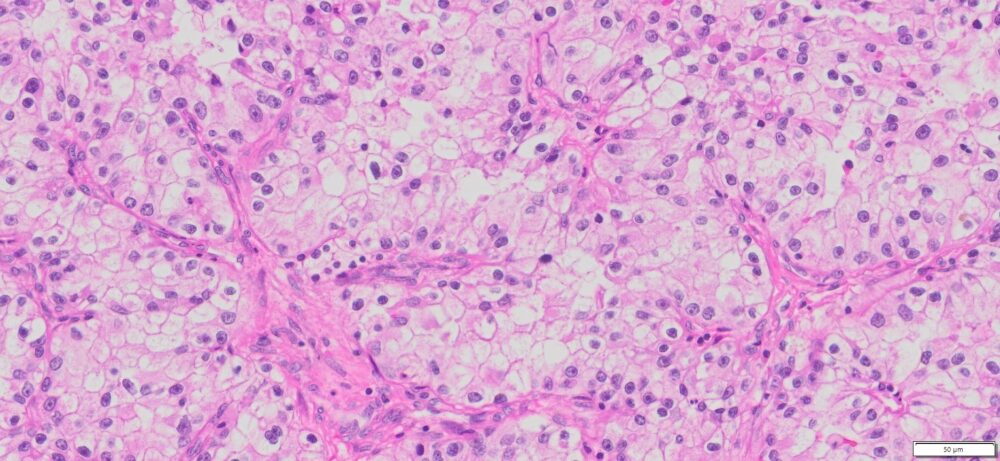

Description

| HuPS-05002T1 | Kidney | Clear –cell renal cell carcinoma | No | Male/56 | 75% | III | pT1apNxMx | NA |